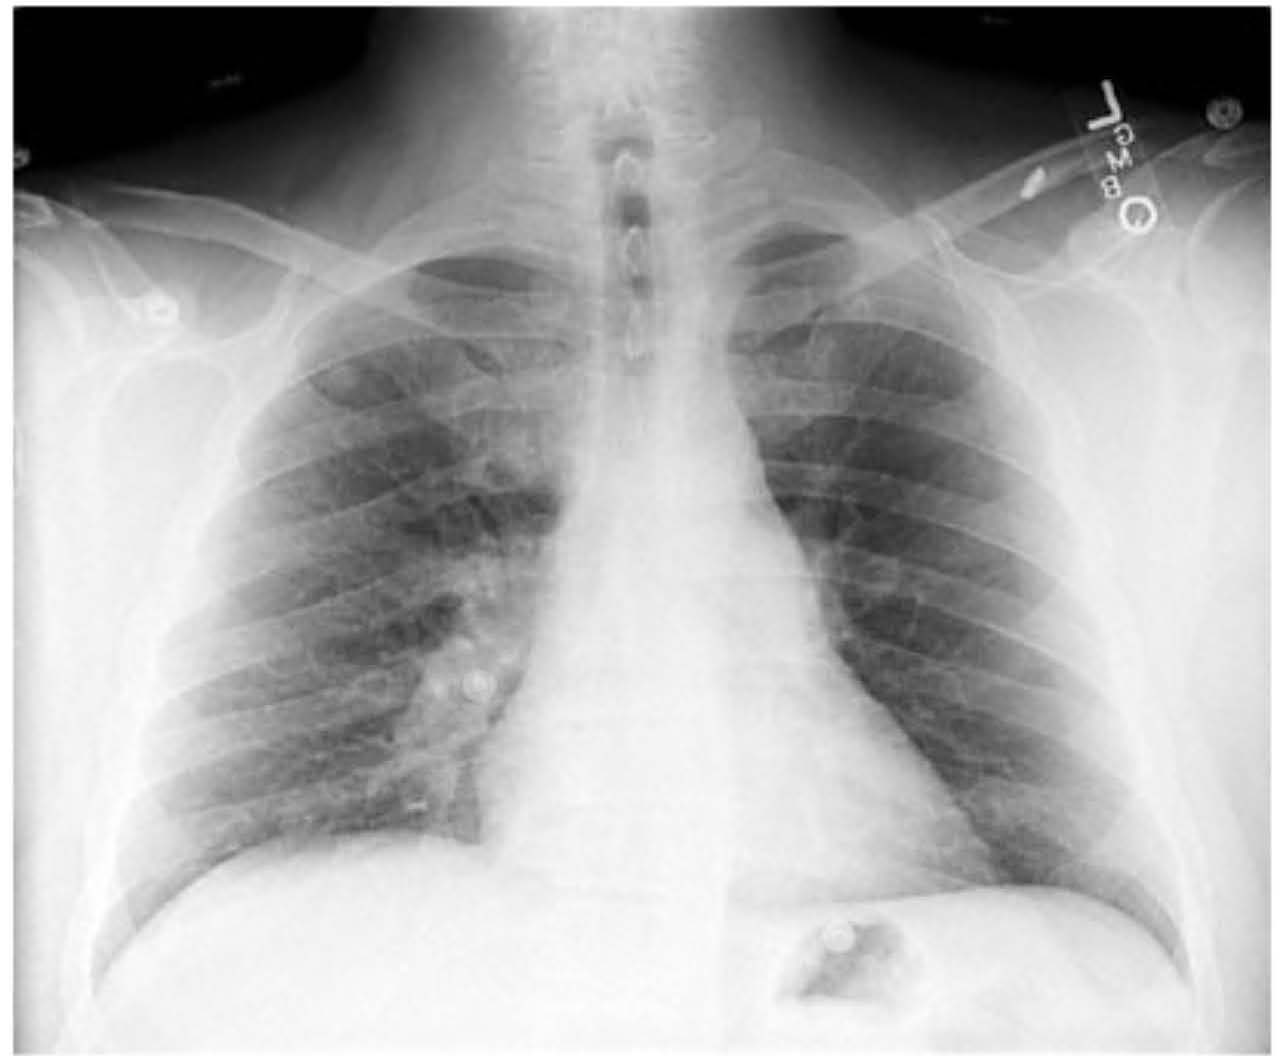

Diagnosis: What diagnosis is most consistent with acute onset severe dyspnea, hypoxemia (SpO2 88%), sinus tachycardia, 1+ bilateral leg edema, recent long-distance immobility (truck driving), and a chest x-ray shown?

Imaging supplement: Show chest x-ray image associated with the case (illustration only).

- Chest x-ray provided as supportive image; chest x-ray alone does not confirm PE

Pulmonary embolism: typical presenting features?

Pulmonary embolism: clinical risk factors that prompt rapid testing (group 1)?

Pulmonary embolism: additional clinical risk factors (group 2)?

Diagnostic test: preferred method to confirm pulmonary embolism?